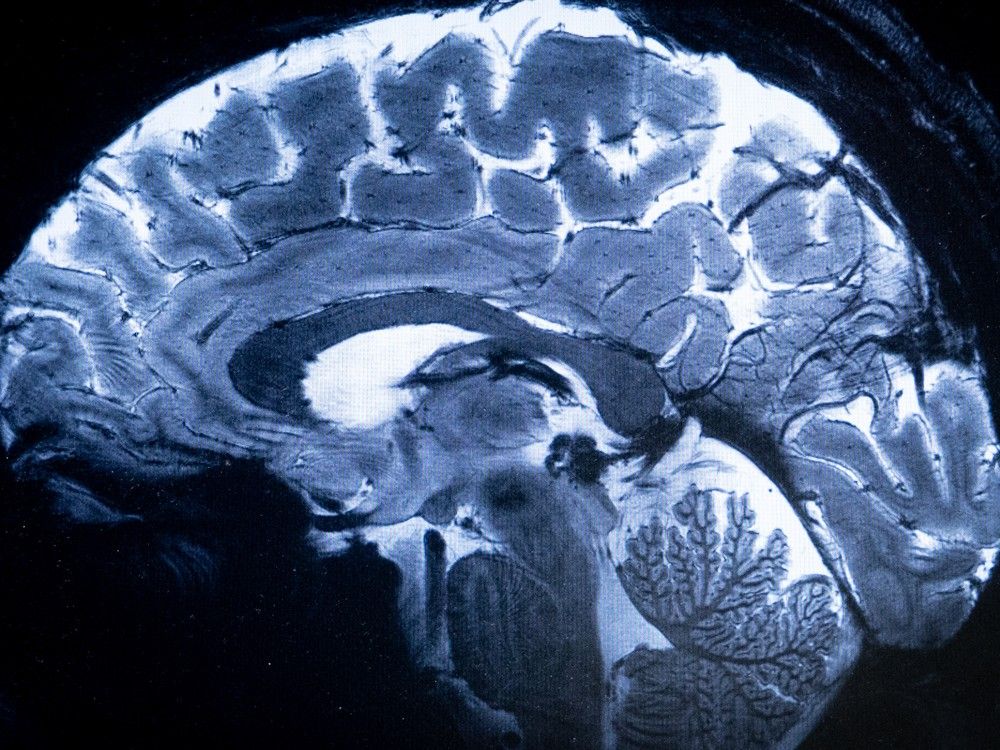

He first explains that nicotine has systemic anti-inflammatory effects on the body and has a direct blocking effect on the Covid-19 virus, i.e. nicotine blocks its entry and proliferation and that using nicotine patches activates the anti-inflammatory system in the body (and mentions acetylcholine, receptors, certain pathways etc.)

If the patient has no side effects, he raises the dose to 7mg for about 1-2 weeks. At this point many of his patients are already feeling really well on many levels: their brain starts working again, their sleep is normalizing, emotions are normalizing, erectile dysfunctions and lack of libido vanish. So when a plateau is reached on 7mg, he increases the dose to 14mg.

Now on to ADHD and hyperactivity in autistic children. He's been using nicotine patches as an integral part of treatment since 2008 in his practice. With children with ADHD and hyperactivity in autism, he starts with 7mg. It's important, he notes, to put the patch on the back between the shoulder blades, as the patches tend to itch and burn a little at the beginning. He speaks of a "dramatic" effect after only a couple of days: kids previously out of control become "sane" again.